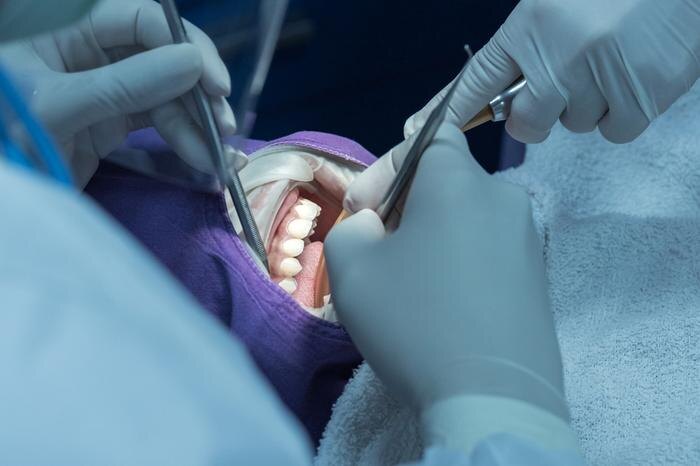

Россиянка рассказала о серьёзных осложнениях после стоматологического лечения в Турции. Девушка хотела установить виниры и получить голливудскую улыбку, но в итоге столкнулась с болезненными последствиями. Об этом сообщает Telegram-канал Baza.

По словам девушки, в марте она обратилась в турецкую клинику для установки виниров. Во время процедуры зубы спилили настолько сильно, что от нижних почти ничего не осталось. Позже пациентка выяснила, что вместо виниров ей фактически установили коронки и мосты на несколько зубов. Уже на следующий день после процедуры появилась сильная боль.

В клинике начали удалять воспалённые нервы — их оказалось целых шесть. Через некоторое время боль вернулась. Таблетки не помогали, поэтому она обратилась в экстренную стоматологию, где врачи обнаружили сильное воспаление и срочно удалили ещё несколько нервов. На следующий день у пациентки сильно опухла щека. Медики предупредили, что инфекция начала распространяться и при более позднем обращении могла потребоваться госпитализация. Кроме того, одна из установленных коронок треснула.

Сейчас ей предлагают новое лечение. Одну конструкцию заменить отдельно нельзя — придётся ломать соседнюю и делать двойную. Стоимость восстановления оценивается примерно в две тысячи долларов, а пока девушке приходится ждать, пока спадёт воспаление.